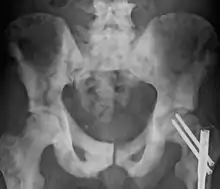

| Sclerosis of the bones of the pelvis due to prostate cancer metastases | |